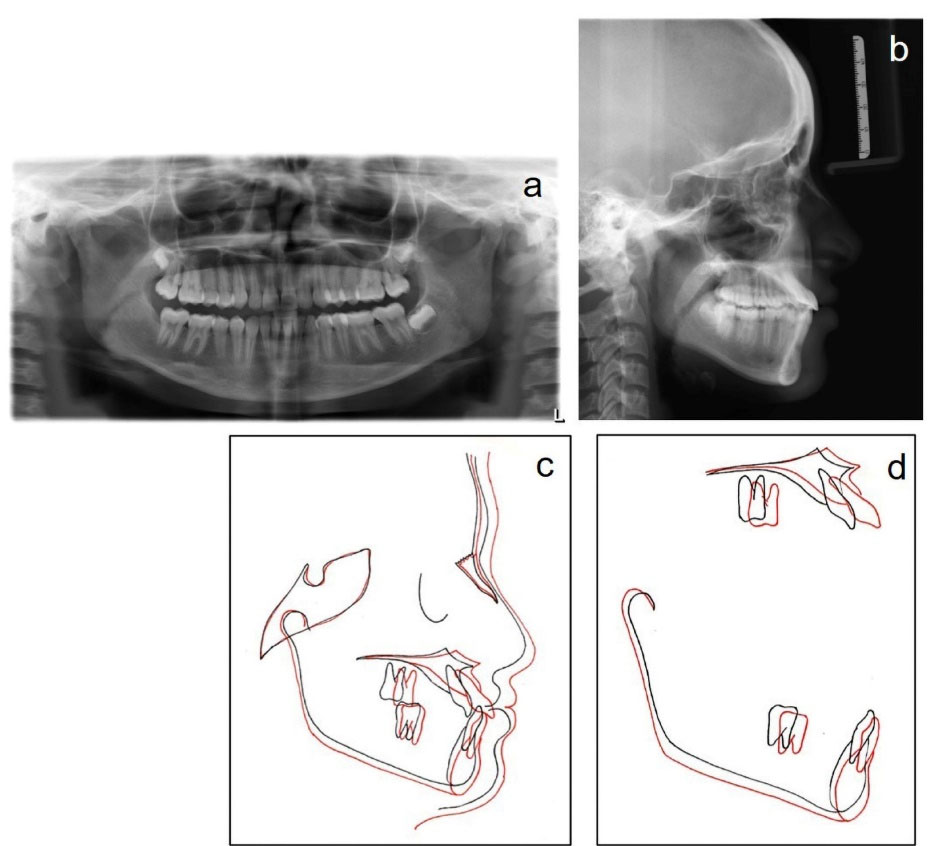

A panoramic radiograph revealed good root parallelism with no significant apical resorption (). Cephalometric superimposition demonstrated improvements in the maxillomandibular relationship (Wits, −8 mm→ -1 mm; ANB, -6° → 1°), the sagittal position of the maxilla (SNA, 76° →79°), and establishment of a harmonious soft-tissue profile along with the clockwise rotation of mandibular base (FMA, 24°; SN-GoGn, 32°) (, , and ).

Figure 7.

Post-treatment radiographs. (a) Panoramic radiograph. (b) Lateral cephalogram. (c) Overall superimposition registered on sella. (d) Regional (best-fit) superimpositions in the maxilla and mandible.